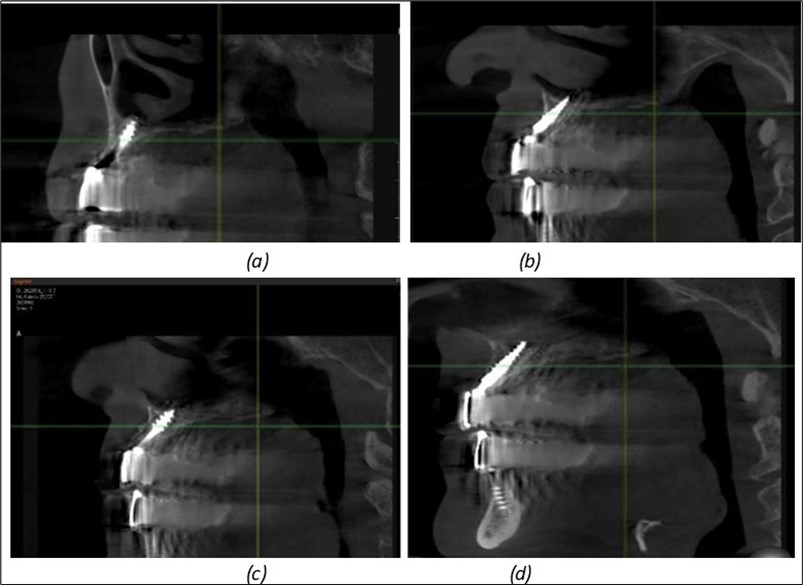

Figure 11.Implants in the anterior area anchored in the nasal cortex (BCS and TPG): (a), (c) – BCS implants fixed in the nasal cortex; (b), (d) – TPG implants fixed in the second nasal cortex with compression in the trabecular area.

Implants in the anterior area anchored in the nasal cortex (BCS and TPG): (a), (c) – BCS implants fixed in the nasal cortex; (b), (d) – TPG implants fixed in the second nasal cortex with compression in the trabecular area.